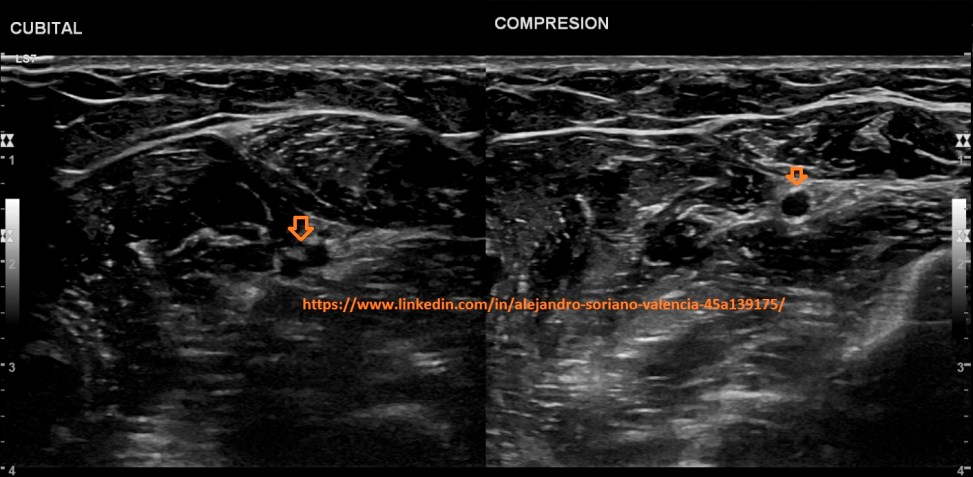

o Cubitales.

Antebrazo extendido en posición anterior.

Cubitals. Forearm extended in anterior position

Tendremos gran dificultad en ver y estudiar las venas radiales y cubitales si no son

patológicas debido a su pequeño tamaño y que con la más mínima presión las

colapsaremos.

El truco está en seguir las correspondientes arterias. Junto a ellas encontraremos dichas

venas (un par por arteria).

We will have great difficulty in seeing and studying the radial and ulnar veins if they are not pathological due to their small size and that with the slightest pressure we will beat them. The trick is to follow the corresponding arteries. Next to them we will find said arteries (one pair per artery). I am looking for good magnifying glasses to facilitate the search of the glasses. Does anyone know of any place where they are at a good price?